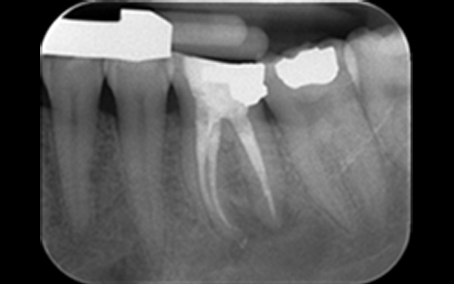

Radiograph 2 2018

Radiograph 2 2023